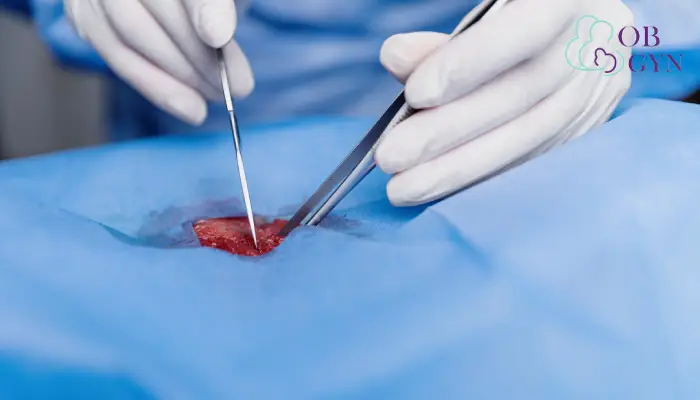

برداشتن کیست

کیست با دقت و بدون آسیب به بافت سالم تخمدان جدا میشود. این مرحله اهمیت زیادی دارد، زیرا حفظ عملکرد طبیعی تخمدان در آینده به آن وابسته است. جراح با مهارت کامل کیست را خارج کرده و از خونریزی یا آسیب به اندامهای اطراف جلوگیری میکند. رعایت دقت در این مرحله، روند بهبودی و موفقیت جراحی را تضمین میکند.